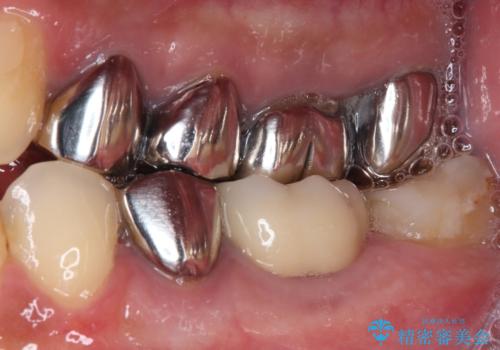

- 下顎左右の奥歯を治療途中で放置してしまっているとのことで来院された患者様です。

欠損部はインプラントによる補綴治療を、土台の外れてしまった歯は、根管治療を行った上で、補綴治療を行うこととしました。

骨格的に下顎が大きく上顎が小さいため、奥歯に力の負担のかかりやすい咬み合わせであるので、治療後は睡眠時にマウスピースを装着することで、セラミッククラウンやインプラント、治療をしたご自身の歯が長持ちするよう指導しています。